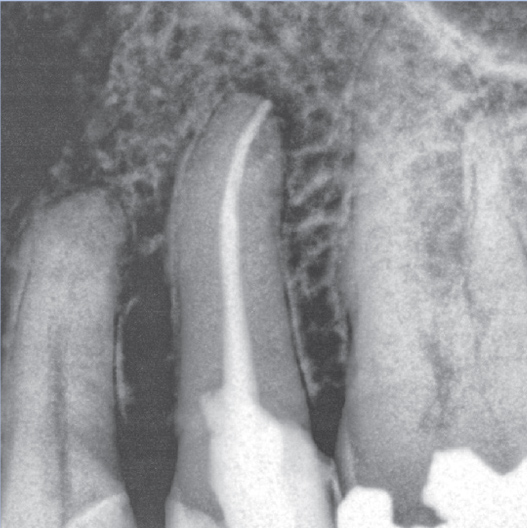

After

After Root Canal treatment